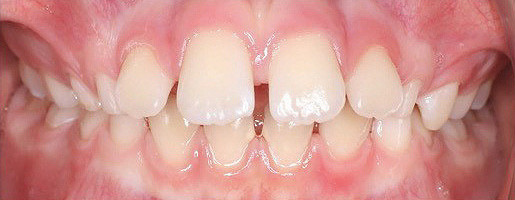

Klinisches Fallbeispiel 1 (Abb. 1a–u)

Neunjähriger Patient mit deutlich vergrößertem Overjet aufgrund eines Distalbisses in Kombination mit einer Protrusion der Oberkieferfront. Habits bzw. myofunktionelle Aspekte wurden adressiert. Die Behandlung erfolgte mit einem Invisalign-Schienensatz (56 Aligner) mit Precsion Wings im Rahmen einer Frühbehandlung zur Prophylaxe eines Frontzahntraumas.